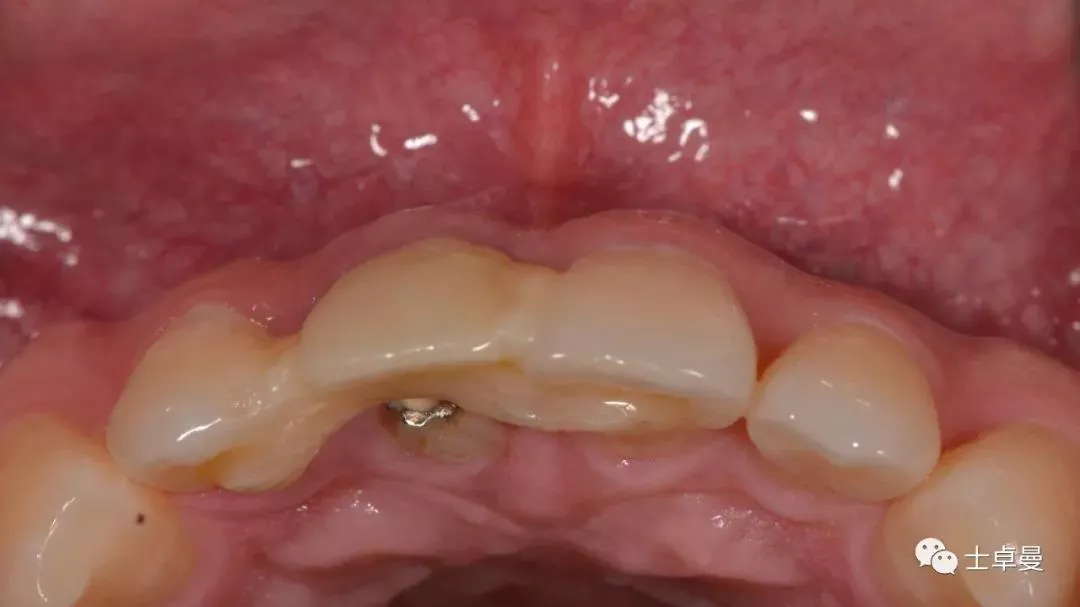

口内检查

· 11牙冠折断,余留残根;

· 唇侧位于龈上2mm,腭侧达骨下1mm,根管内封药存;

· 探(-),冷 (无反应),叩 (-),松 (-),牙龈可;

· 中位笑线,牙龈生物型为中弧形、中厚龈生物型;

· 其余牙及口腔卫生尚可。

上部制作马里兰桥临时修复体

术后10天复查,软组织无炎症

术后1个月,取下马里兰桥,可见骨弓轮廓可,软组织无炎症